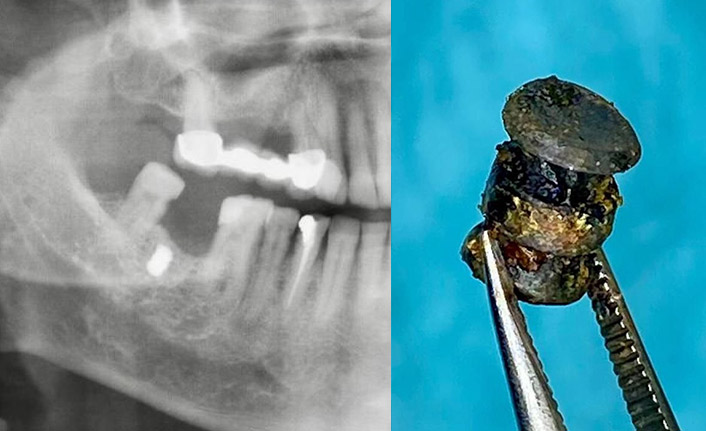

21 Ocak 2021'de akşam saatlerinde Pamukkale ilçesinde doğal gaz tesisatçısı Burak Durna, Cumhuriyet Mahallesi'ndeki evine gireceği sırada yan binadaki boş daireden tabancayla ateş edilmesi sonucu ağır yaralandı. Durna'yı kapı önünde kanlar içinde eşi Seher Durna buldu. Ambulansla Pamukkale Üniversitesi Hastanesi'ne kaldırılan Durna, hayatını kaybetti. Olayın aydınlatılması için Denizli Emniyet Müdürlüğü geniş çaplı çalışma başlattı. Olay Yeri İnceleme ile Cinayet ve Gasp Büro Amirliği ekipleri, Durna'nın saldırıya uğradığı bina ve çevresinde detaylı inceleme yaptı.

Şüphelinin, Burak Durna'ya ait evin yanındaki apartmanın 1'inci katındaki boş dairenin balkon kapısını kırıp, içeriye girdikten sonra pusuya yattığı belirlendi. Cinayetin aydınlatılması için özel ekip kuruldu. Cinayet Bürosu ekipleri, olayı çözmek için Durna'nın başta yakınları olmak üzere arkadaşlarının da ifadesini aldı. Ekipler fail ya da faillerinin tespit edilip, yakalanması için çalışmalarını sürdürüyor.